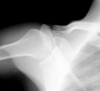

Type I injuries involve purely an AC joint sprain with intact CC ligaments. Type II injuries involve complete tearing of the AC joint and a sprain of the CC ligament with the CC measurement being < 25% greater than of the contralateral shoulder. Type III, IV, V, and VI injuries all involve complete tearing of both the AC and CC ligaments. Type III injuries have a CC distance measurement between 25 and 100% greater than that of the contralateral side (this patient) compared to Type V injuries which have a CC distance > 100% of the contralateral side. Type IV and VI injuries represent posterior and inferior dislocation of the clavicle, respectively. The coracoacromial ligament is generally spared in these injuries